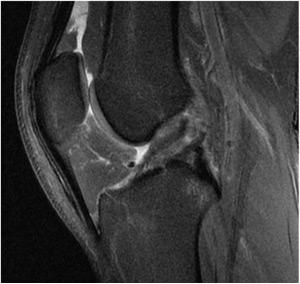

- Modified Lemaire Lateral Extra-Articular Tenodesis Using an Inlay Technique and All-Suture Knotless Anchor Fixation

- Primary Anterior Cruciate Ligament Repair: Current Concepts

- Arthroscopically Assisted Fixation of Terrible Triad Variant Injuries of the Elbow With Small-Bore Needle Arthroscopy

- Osteochondral Allograft Transplantation Of Posterior Femoral Condyle Lesions Utilizing An Open Posterior Approach To The Knee

- Modified Bosworth Technique for Medial Collateral Ligament Reconstruction of the Knee Using Semitendinosus Tendon Autograft

- Quadriceps Tendon Allograft for ACL Reconstruction With and Without a Bone Block

Photo Gallery